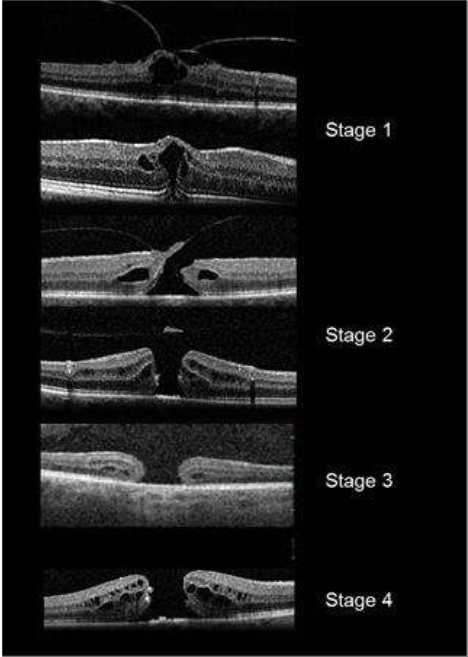

Qual é a classificação do Buraco de Macula?

Classificação de Gass

Estágio 1: Buraco macular iminente

- 1a: Pseudocisto foveal

- 1b: Descontinuidade da retina externa (até 300 micrômetros)

Estágio 2: BM<400 micrômetros + Hialóide aderida à fóvea

Estágio 3: BM > 400 micrômetros + Hialóide solta da fóvea mas permanece aderida ao disco

Estágio 4: BM + DVP completo